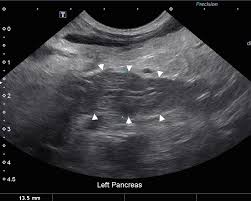

Treating Pancreatitis In Dogs The Bark from static.thebark.com Older breeds and spaniels are predisposed. A dog with pancreatic cancer may show signs such as: Eliza reiss grant, dvm, and kristine e. Diagnosing canine pancreatic cancer your vet will use blood tests to check for pancreatic cancer. He will conduct further tests and investigations and reach the root cause. Today our clemmons vets explain the types of pancreatic cancer seen in dogs. Your veterinarian will also perform abdominal radiographs in order to determine the presence of any masses or changes in the pancreas tissue. A cancer diagnosis for your dog is heartbreaking and often overwhelming.

Make a note of any lumps and bumps. Burgess, dvm, diplomate acvim (oncology) tufts university. The symptoms of pancreas problems in dogs can easily be mistaken for other digestive problems because most of the digestive issues come with the same or similar symptoms. Insulinomas are usually diagnosed with the finding of hypoglycemia with normal to high insulin on bloodwork and concomitant clinical signs. A cancer diagnosis for your dog is heartbreaking and often overwhelming. The diagnosis of pancreatic cancer in dogs will be achieved through a physical examination and examination of current symptoms and previous medical history. A dog with pancreatic cancer may show signs such as: Diagnosis of pancreatic cancer in dogs your vet will likely try to see if he or she can feel a protruding mass in the abdomen, which can be a symptom of adenocarcinomas in the pancreas. Benign exocrine pancreatic tumors are rare. Both tumors are more common in dogs than cats. Symptoms of pancreatic cancer in dogs if your dog is diagnosed as having a pancreatic tumor it means that the cells within a specific part of your pup's pancreas are overproducing (reproducing excessively). Older breeds and spaniels are predisposed. A determination of the lipase (an enzyme released by the pancreas) level will assist your veterinarian in the diagnosis, as it is often elevated in a majority of patients with pancreatic adenocarcinoma.